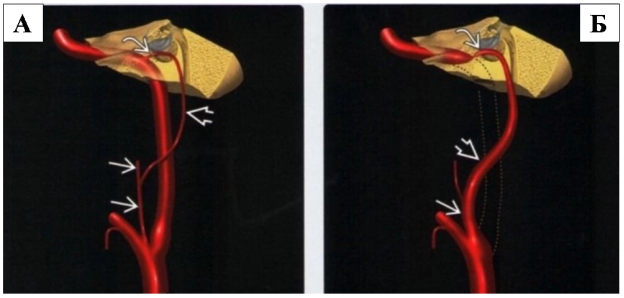

Рис. 2

На рисунке 2А в боковой проекции представлена нормальная внутренней сонной артерии (шейный и каменистый отделы ВСА), а также нижняя барабанная артерия, которая отходит от восходящей глоточной артерии, проходит в височную кость и анастомозирует с очень мелкой сонно-барабанной артерией в области мыса улитки.

На рисунке 2Б в боковой проекции пунктирными линиями представлены аномалии развития шейного отдела внутренней сонной артерии (ВСА). В норме кровоснабжение осуществляется альтернативными коллатералями: восходящей глоточной, нижней барабанной и сонно-барабанной артериями. Указанные особенности характерны для аберрантной внутренней сонной артерии (АбВСА).